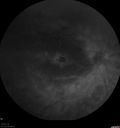

FUNDUS AUTO FLUORESCENCE: The fundus auto fluorescence images show patches of hypo auto fluorescence, predominately in the superior periphery with some hyper auto fluorescence around the macula in the mid periphery.